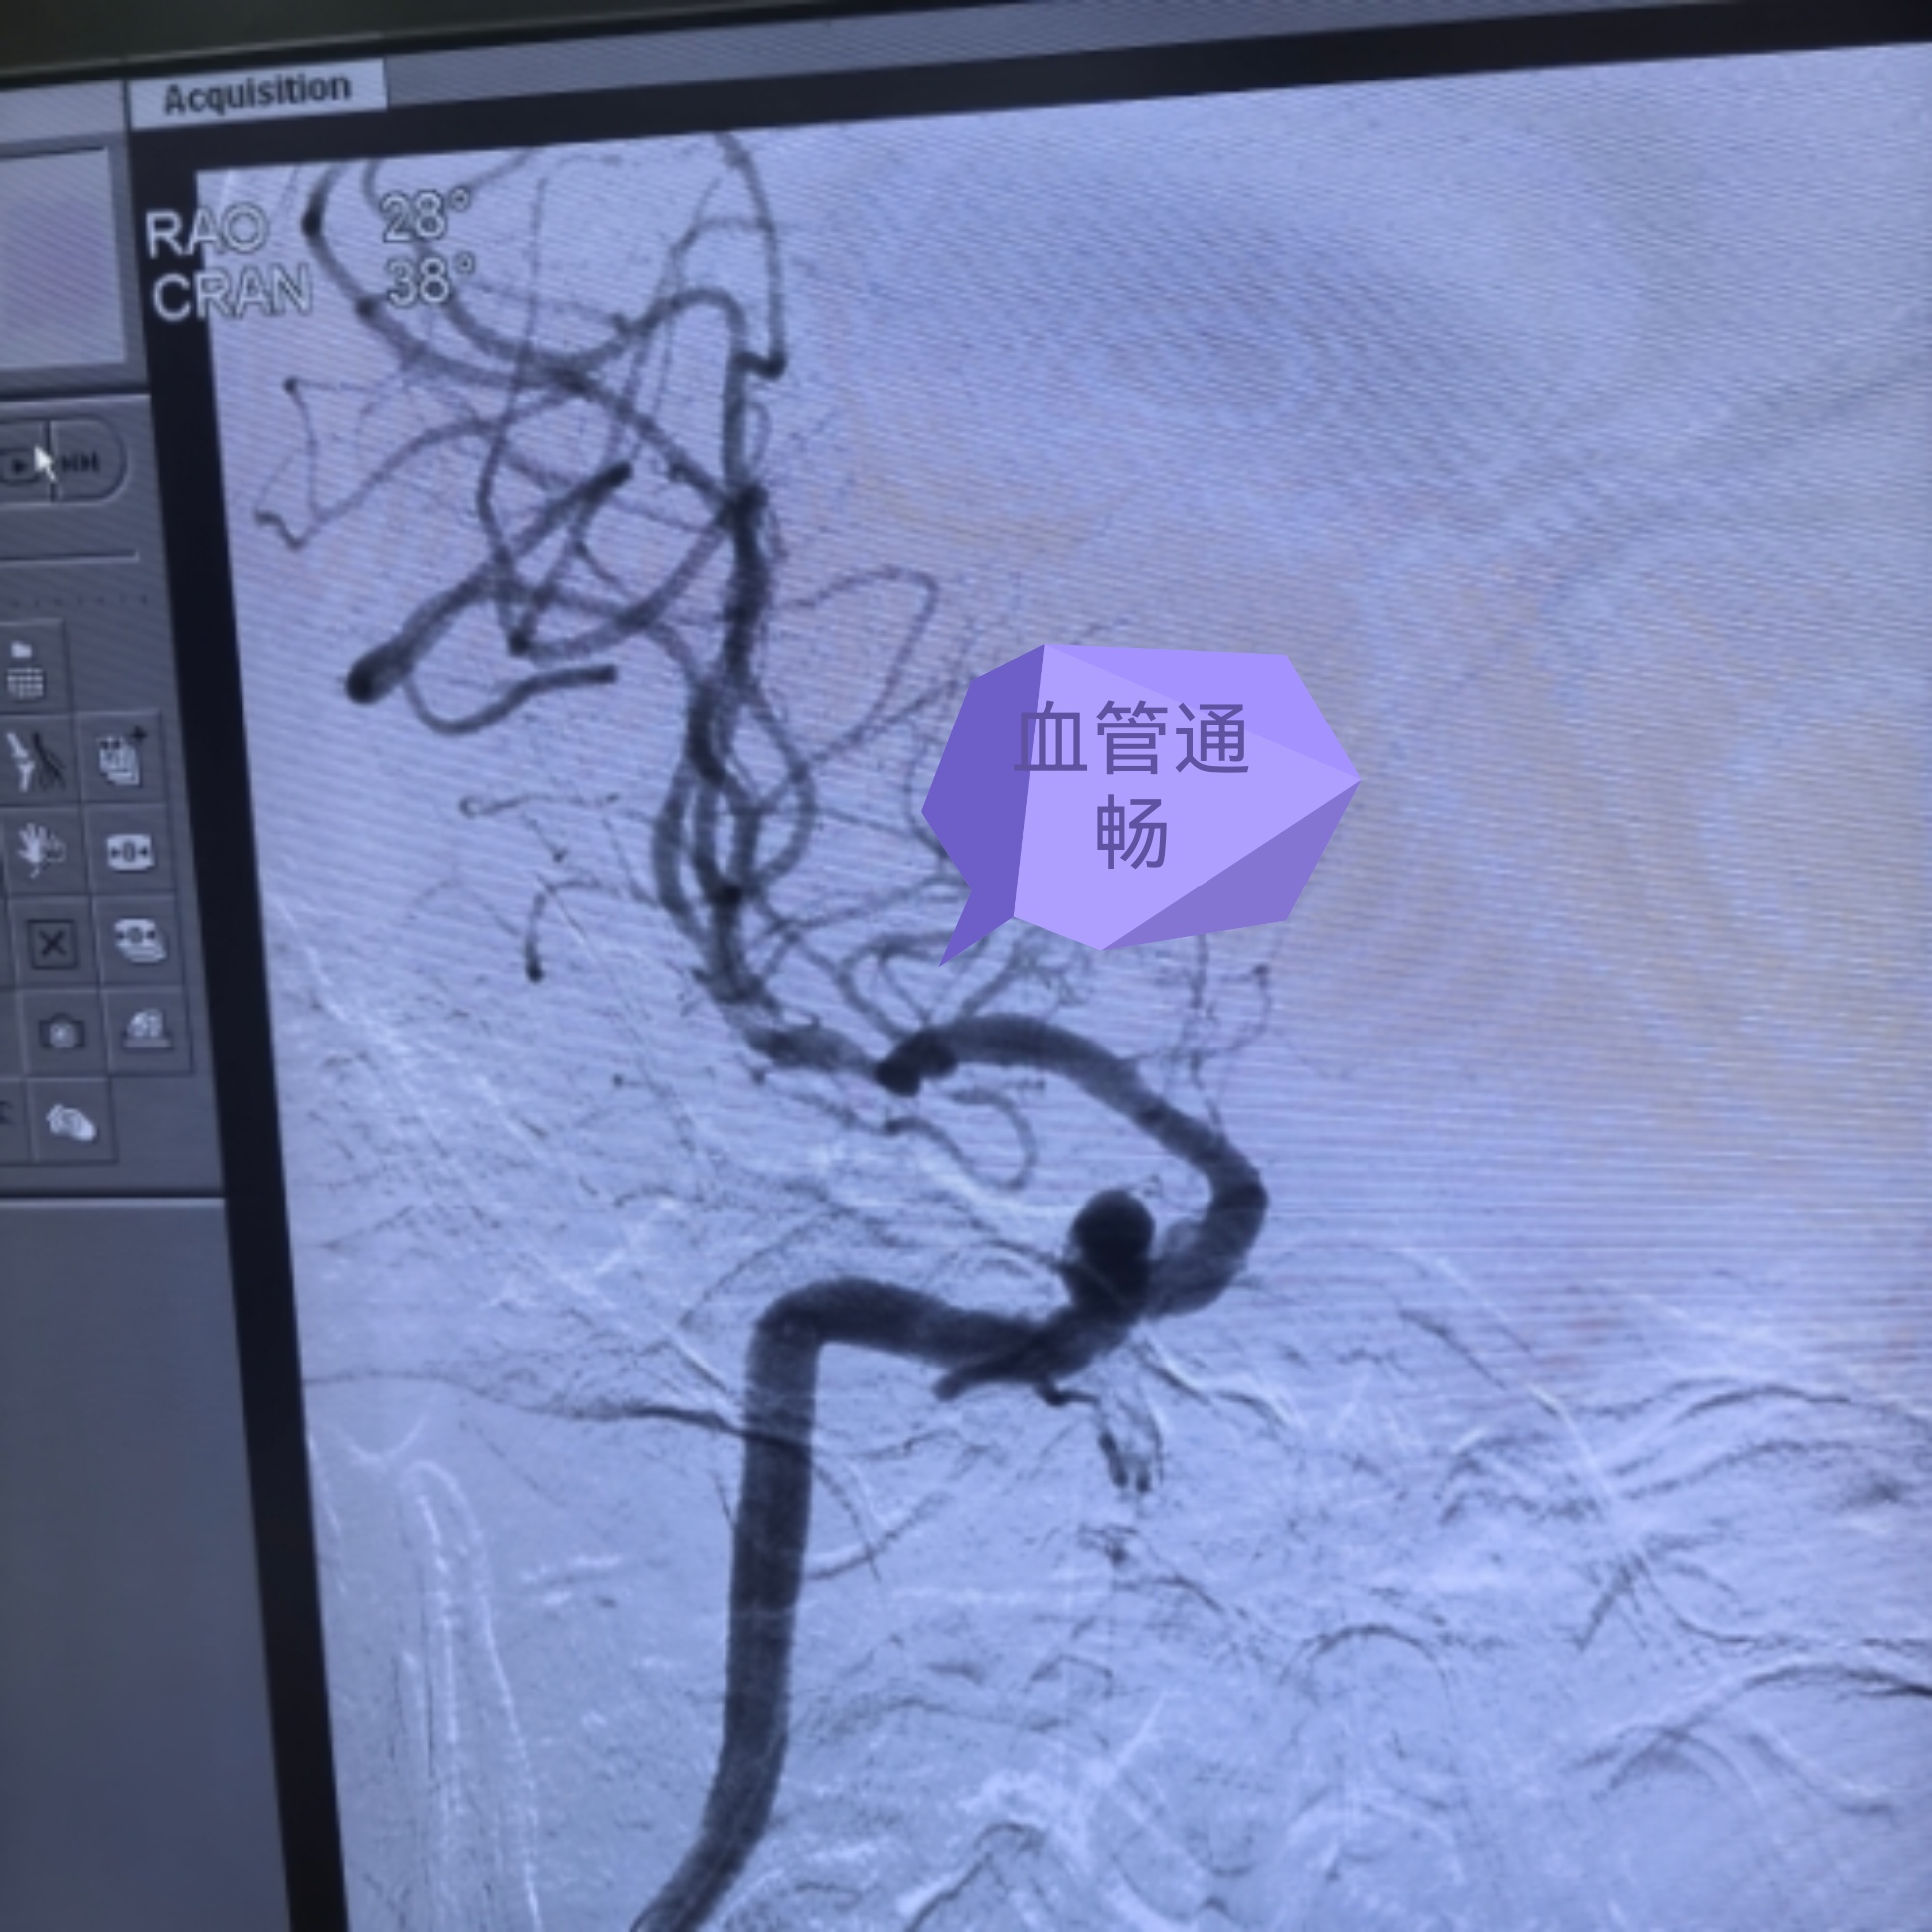

次日凌晨5:00,第四台急诊手术接力开展,患者为左侧大脑中动脉闭塞,且颈总动脉起始段极度扭曲,同时合并大脑中动脉原位狭窄,手术难度极大。团队迎难而上,顺利完成取栓手术并行颅内球囊扩张,成功打通生命通道。

大家常说,时间就是大脑。对于卒中患者而言,早一分钟开通血管,就多一分康复的希望。我们深知,多争取一秒,患者就少一分残疾,多一分回归家庭的可能。凭借成熟的卒中中心建设、规范的绿道流程,以及过硬的介入技术,三台取栓手术均获成功。患者术后血管再通,肢体功能迅速恢复,从昏迷瘫痪到恢复自如,真正实现了“入院重危,出院安康”。